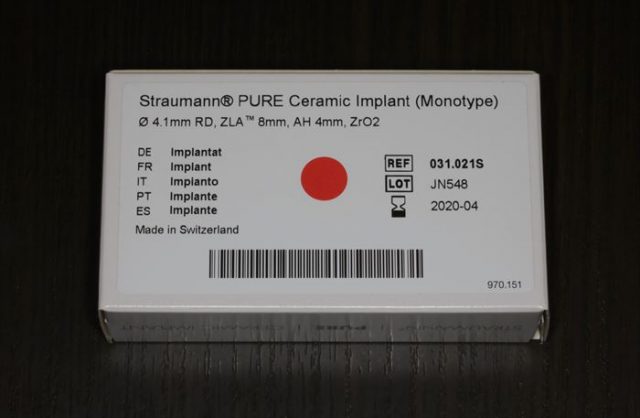

ストローマン ピュア セラミック インプラントを用意します。

挿入ジグをスナップフィットさせ、ジルコニアインプラントをピックアップします。